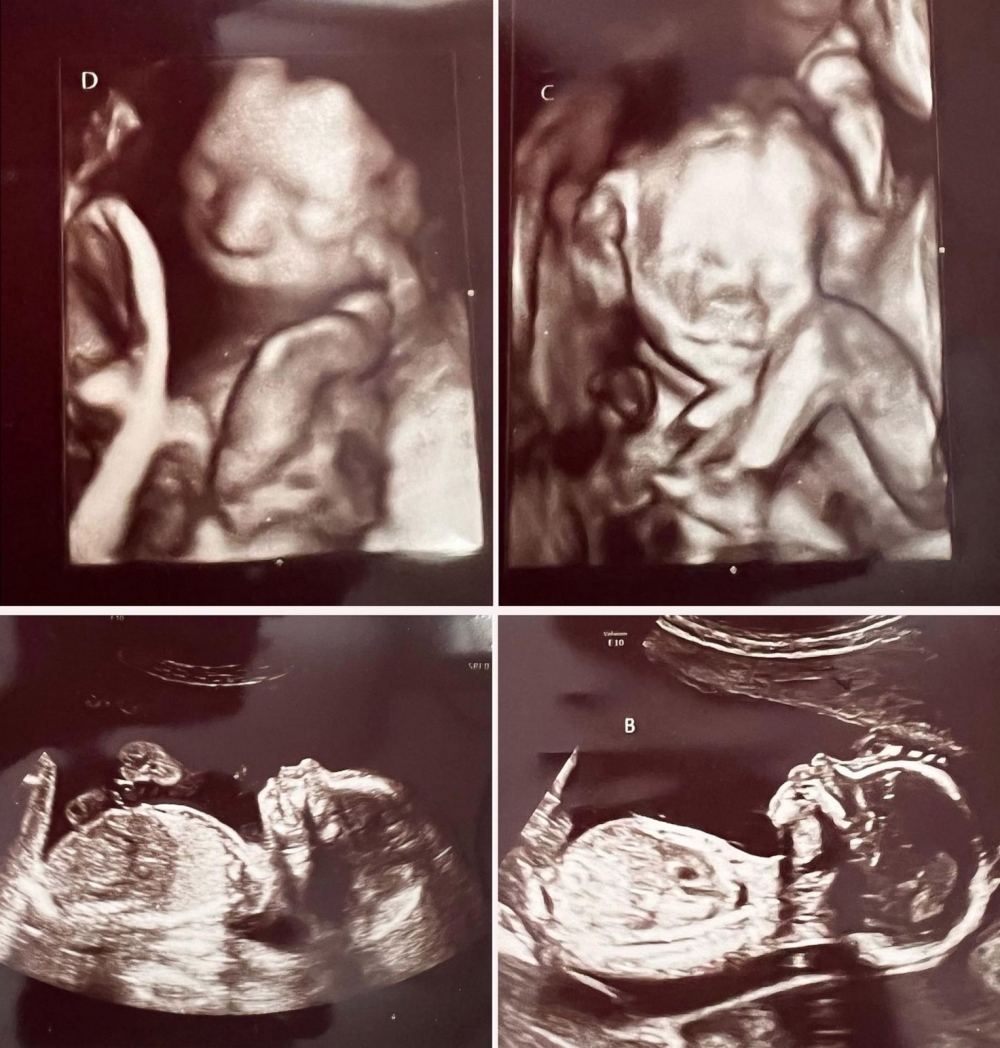

Ashley進行了首次超聲波檢查,當她發現醫護人員在報告上寫下「A」、「B」字眼後,立刻詢問對方自己是否懷上雙胞胎,結果對方一臉平靜回答:「沒錯,親愛的,你有四個小孩。」Ashley坦言當下只感到天旋地轉,「我感覺快暈倒了!」

超聲波檢查證實Ashley成為七千萬分之一的幸運兒,成功懷上2對同卵雙胞胎,分別是2男2女。不可思議的事件導致她走出病房後,還上網查詢事情發生的可能性,更因為過去的流產經歷,暫時不打算將此事告知孩子父親。對於能夠懷上四胞胎,Ashley除了驚訝,還有許多複雜感觸:「我流產了4次,而我親愛的祖母在一個月前離開了,我覺得這似乎是她送給我的禮物,就像彌補我過去所遭受的損失。」